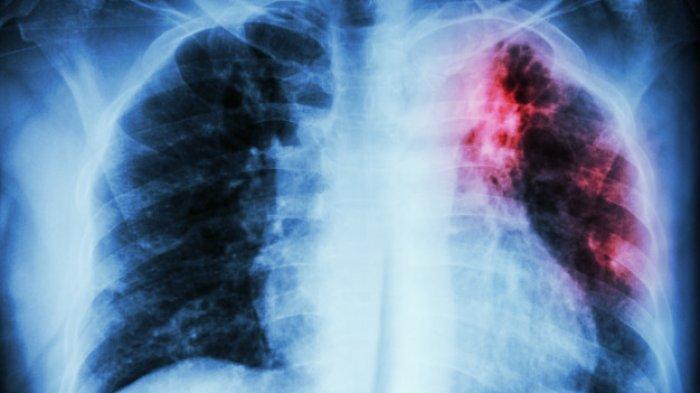

TRIBUNMANADO.CO.ID, MANADO - Tak hanya penyakit Covid-19 yang berbahaya, di Indonesia tuberkulosis (TBC) cukup menjadi penyakit yang dikhawatirkan banyak orang.

Bahkan menurut dr Maria Simanjuntak, seharusnya kita lebih takut dengan penyakit TBC.

Ya, TBC sendiri memang membutuhkan waktu lama untuk bisa sembuh.

Selain itu biasanya perawatannya membutuhkan waktu minimal enam bulan hingga 12 bulan.

Obatnya pun tak main-main, bisa sampai lima jenis obat mulai dari obat anti TBC hingga obat pengikut lainnya.

Hal tersebut karena biasanya pasien TBC mengalami banyak gejala mulai dari batuk hingga efek samping yang ditimbulkan dari obat lain.